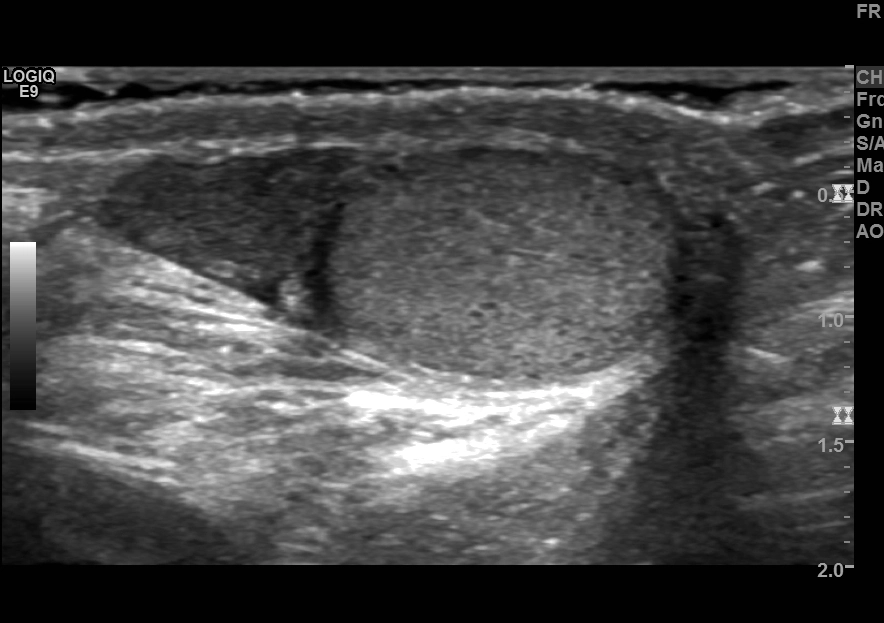

Áp xe mào tinh (Epididymal abscess)